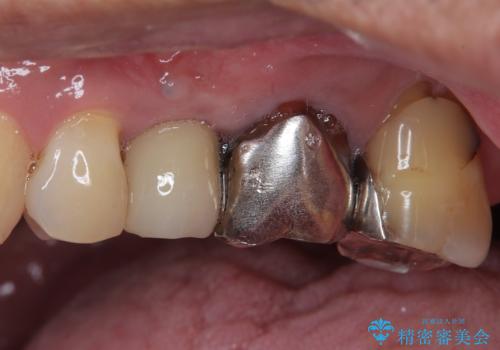

抜歯が必要な小臼歯 インプラントによる補綴治療

- 頻繁に銀歯が外れてしまうとのことで来院された患者様です。

歯肉の中、深いところまでむし歯が進行しており、歯根を部分矯正で引っ張り出してから補綴治療を行うか、抜歯してインプラント補綴治療を行うか選択することになりました。

海外での勤務があり、部分矯正は困難とのことで、インプラントによる補綴治療を行うこととしました。

より審美的で、より機能的に優れた治療をご希望とのことであったので、ジルコニアカスタムアバットメントを用いたインプラント治療を行うこととしました。